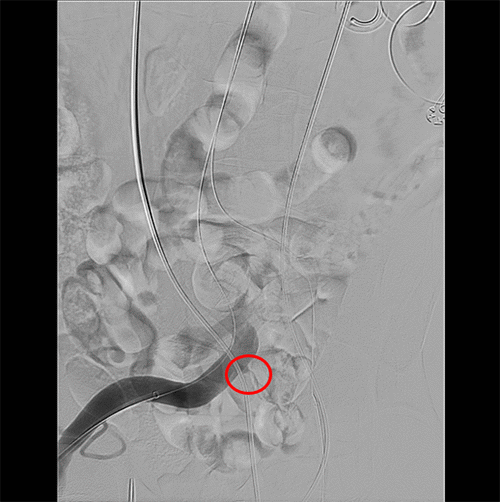

A 63-year-old male with a history of recurrent rectal cancer with metastases, abdominoperineal resection, chemoradiation, deep vein thrombosis on apixaban, pancytopenia, and retroperitoneal fibrosis with ureteral stents presented to the emergency department with fatigue. He had hematuria for ten months, attributed to urinary tract infections (UTIs). On exam, he was hypotensive, with abdominal scars, a parastomal hernia, and hematuria in his urinary catheter. His hemoglobin was 8.3g/dL from a baseline of 9.0g/dL, and his urinalysis demonstrated pyuria and later grew Enterococcus. The critical care team admitted him to the intensive care unit on norepinephrine with suspected urosepsis. His hypotension resolved after resuscitation and treatment with vancomycin, cefepime, and metronidazole. His fatigue and hematuria persisted, and he had a non-contrast CT demonstrating hydronephrosis. He underwent a ureteral stent exchange, but he developed bleeding from the right ureteral orifice during the procedure. This insult resulted in tachycardia, hypotension, and a drop in hemoglobin from 7.6g/dL to 6.7g/dL, requiring a packed red blood cell (PRBC) transfusion. At this point, a fistula was suspected but not confirmed. He had a CT angiogram (CTA), which demonstrated a thrombus in the right ureter, contrast in the renal pelvis bilaterally from his cystogram, and hydronephrosis bilaterally; however, he had no extravasation of contrast. An angiography was planned for later in the week. A few days later, he received nephrostomies for persistent hydronephrosis. He developed bleeding again and required two units of PRBCs for a hemoglobin of 6.4g/dL with an appropriate response of 8.3g/dL. He stabilized before going to the endovascular suite the next day. Pelvic angiography identified a fistula between the ureter and the right external iliac artery (Figure 1). A 16 mm × 14 mm × 7 cm Gore iliac limb extension was placed without jailing the hypogastric (Figure 2). He no longer had bleeding from his urethra. He was discharged on aspirin and amoxicillin clavulanate at the recommendation of an infectious disease consult based on a history of UTIs. Unfortunately, this patient passed a month later from unknown causes, and there was no follow-up in that interval.

Figure 2. Resolved Fistula with Iliac Limb. Published with Permission